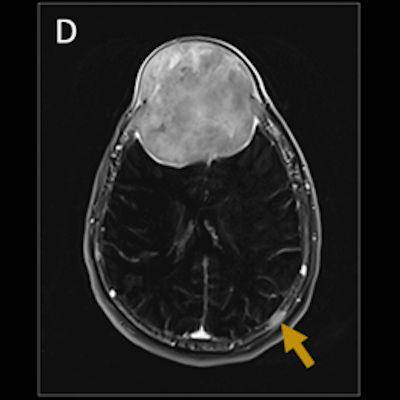

- Aksiyel kontrastsız (A) ve aksiyel kontrastlı (B) T1A görüntülerde frontal bölgede anteriorda cilt altına posteriorda ekstraaksiyel mesafeye uzanan diffüz homojen kontrastlanan lezyon izlendi (oklar). Aksiyel T1A kontrastlı görüntüde (C) mezensefalon düzeyinden geçen başka bir kesitinde sağ frontal kemik zigomatik proceste (ok), aksiyel subtraction (D) görüntüde sol parietal kemikte (ok) ve sagittal substraction (E) görüntülerde C2 vertebra korpusunda (ok) benzer kontrastlanma paterninde ayrı lezyonlar saptandı.

- Frontal lobdaki lezyonun aksiyel T2A görüntülerde (F) heterojen düşük sinyalli olduğu (ok) ; difüzyon (G) ve ADC (H) görüntülerde silik periferik difizyon kısıtladığı (oklar) gözlendi.